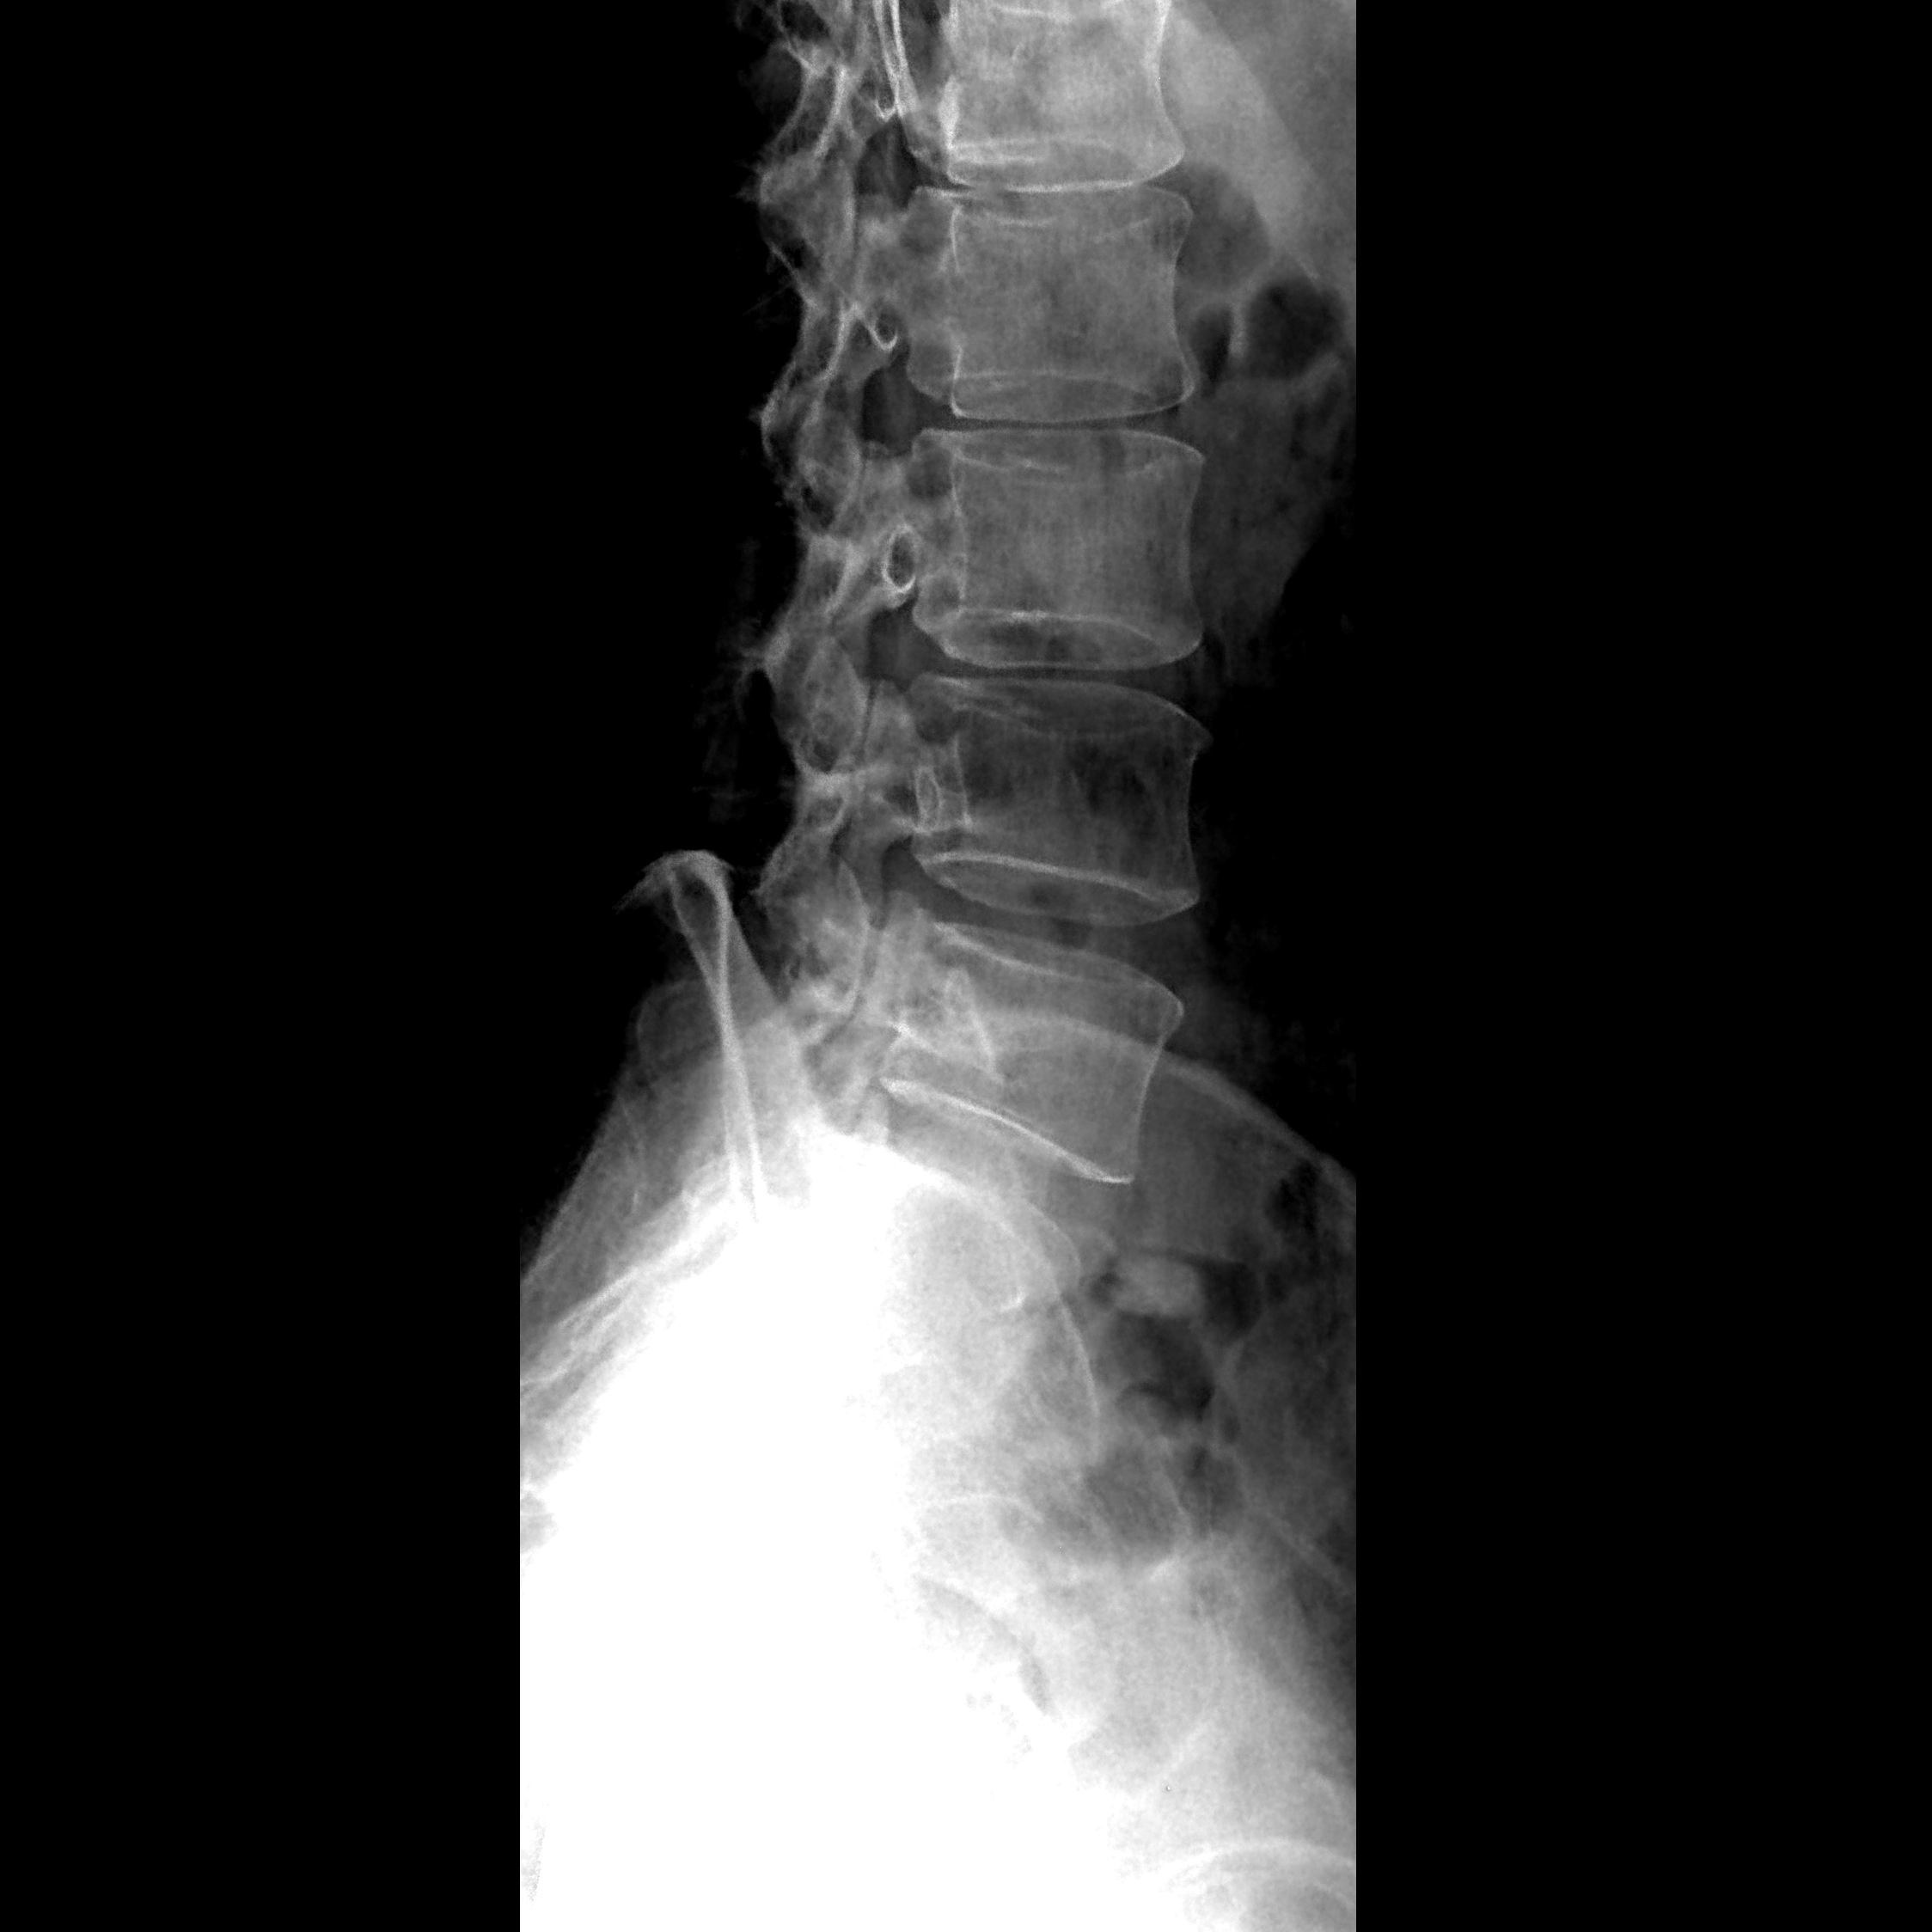

kV(千伏)的增加会增强射线的穿透力,但同时也会增加散射线,影响图像对比度。需要根据患者的体型、病变部位等因素合理设置kV值。

mAs(毫安秒)的增加会增强信号,但过高的mAs值可能导致曝光过度,图像发黑。因此,需要根据实际情况调整mAs值,以获得适当的图像亮度。

滤线栅是吸收散射线的部件,能有效减少图像上的灰雾,提高对比度。在拍片过程中,应确保滤线栅正常工作,以提高图像质量。